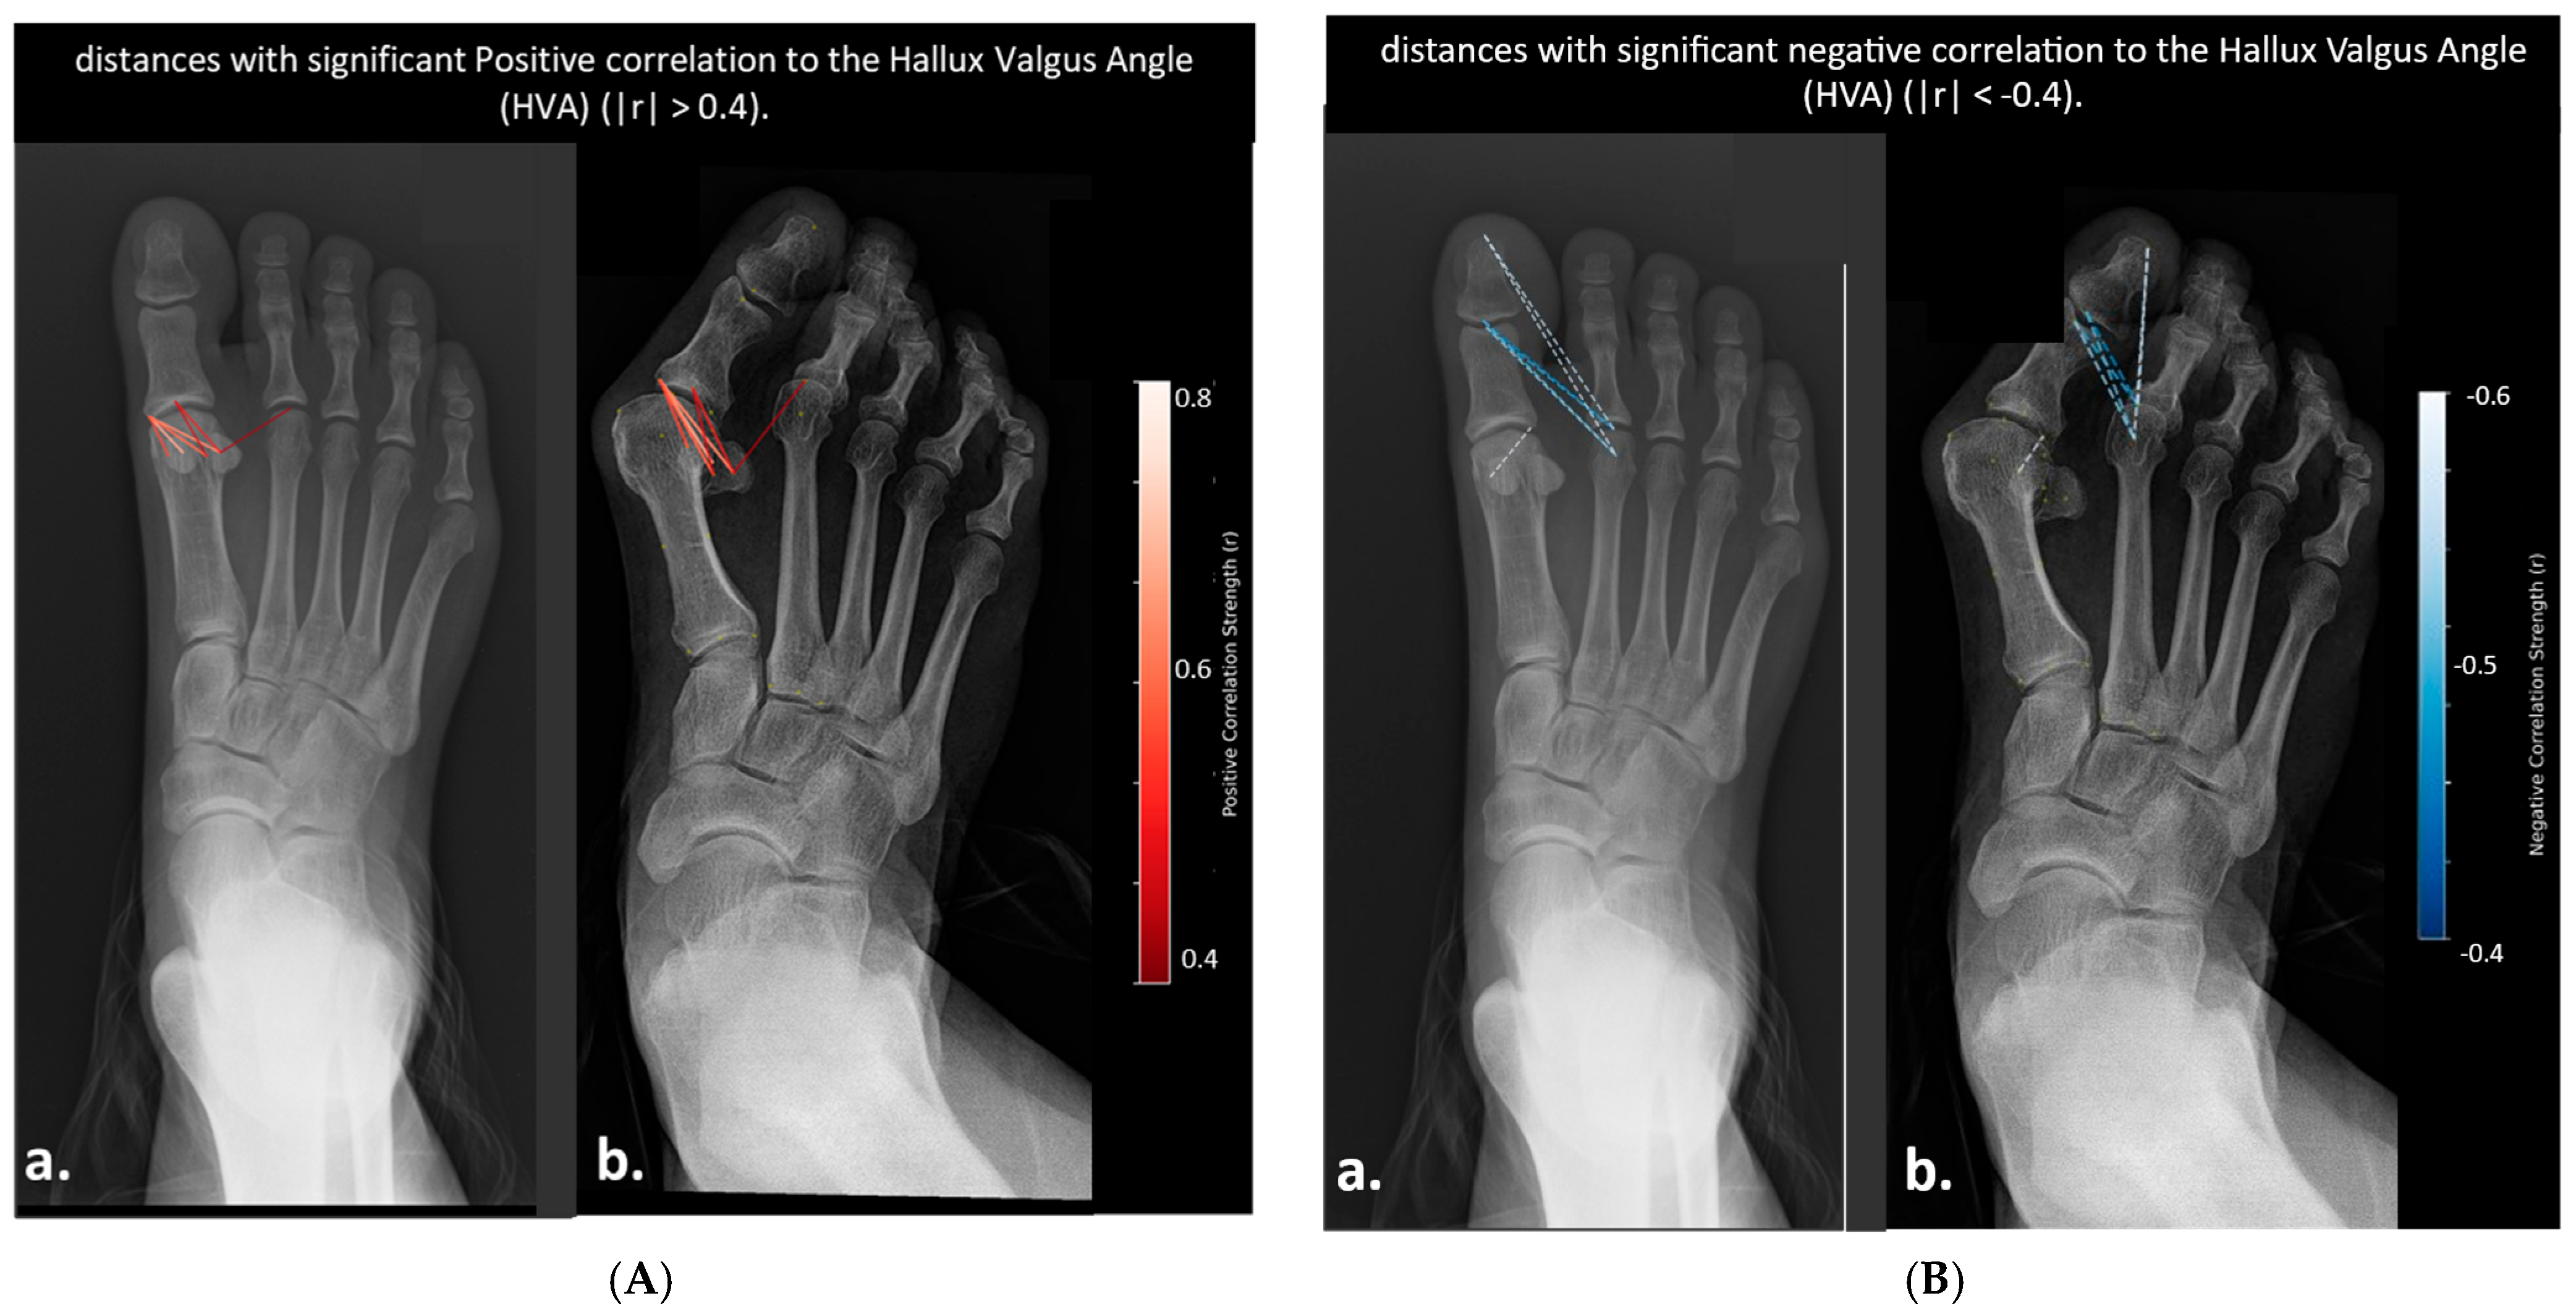

- Distances Correlated with Hallux Valgus Angle (HVA)